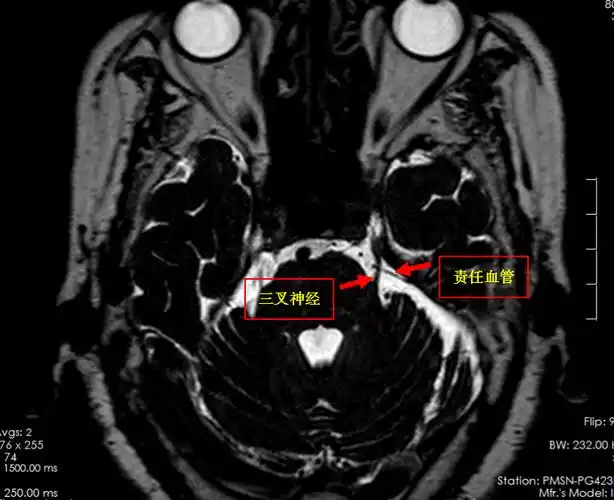

我院mr三叉神经薄层扫描提示:患者左侧三叉神经颅内段内侧缘小血管骑

其它 学以致用,方便他人,快乐自己! 写美篇三叉神经痛的病因在哪里?

对付三叉神经痛,这里有个经典手术

唐都医院神经外科王景19年三叉神经痛两处责任血管压迫

术前磁共振影像,黄色表示三叉神经,红色表示周围血管,相互关系紧密.